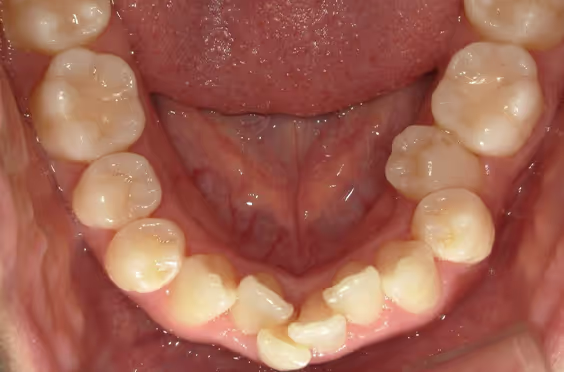

- 症例1

治療期間 4カ月

治療費 23.1万円(月額1,925円~)

※上顎前歯部、下顎前歯部の叢生をマウスピース型矯正装置で改善したケース。矯正治療上のリスクとして、治療中の虫歯、歯根吸収、歯肉炎 ・歯周炎の発生などが考えられる。